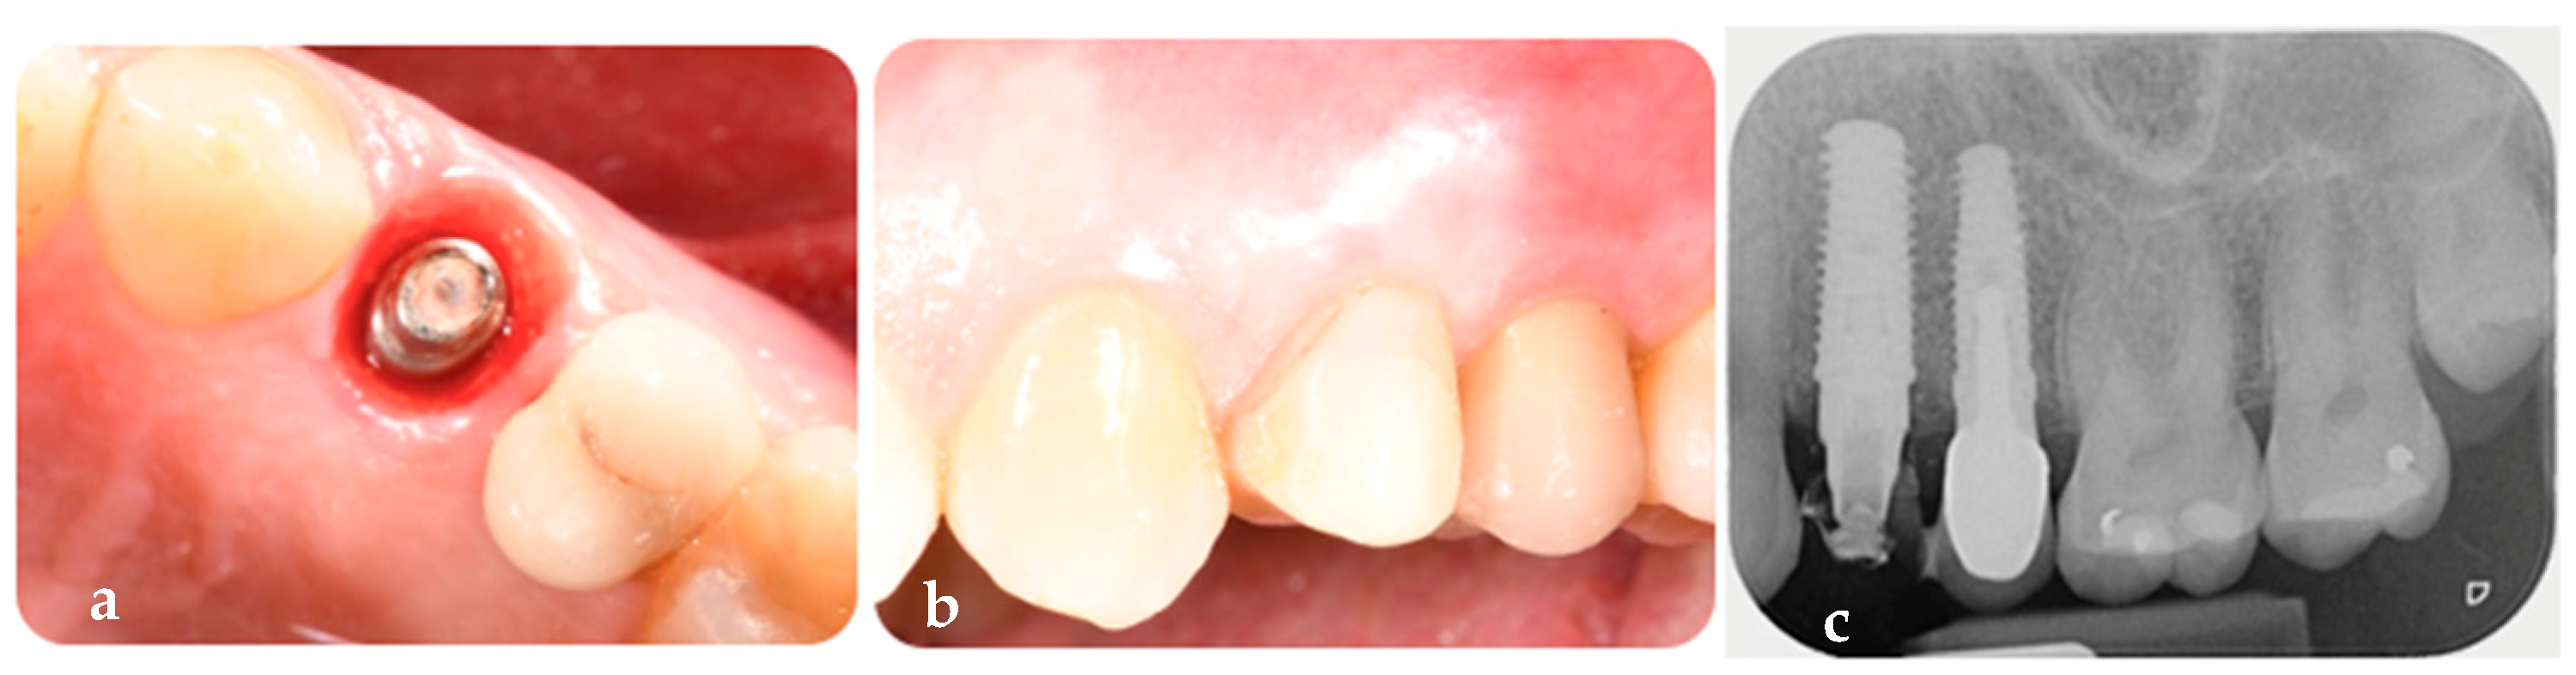

2.1.3. Phase 3: Finalization of Aesthetics on the Definitive Framework and Follow-Up

2.2. Measurements

- Absence of mobility of the prosthesis, abutment, and implant at both 6-month and 1-year follow-up.

- Presence of keratinized peri-implant on the mid-buccal and mid-lingual aspects at 6-month and 1-year follow-up.

- Sulcus Bleeding Index (SBI) score of 0 at both 6-month and 1-year follow-up.

- Modified Plaque Index (mPLI) score of 0 at both 6-month and 1-year follow-up.

- Probing Depth (PD) < 4 mm at both 6-month and 1-year follow-up.

- Keratinized mucosa width (KMW) values of 4 mm before surgery, 4 mm at 6 months, and 5 mm at 1 year after implant, customized abutment, coping, and restoration placement.